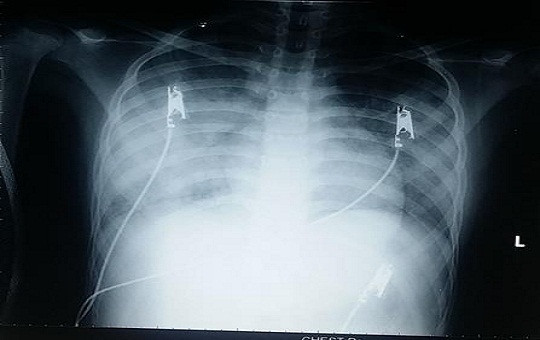

Do bé đã chụp CT scan thực quản - dạ dày không thấy bất thường nên các bác sĩ tiến hành cho bé chụp CT scan ngực thì bất ngờ phát hiện đường rò đường mật – khí quản. Ngay sau đó, bé được nội soi phế quản, thấy lỗ rò từ carina (nơi khí quản chia đôi vào phế quản trái và phải), bơm thuốc cản quang vào lỗ rò và chụp X-quang thấy thuốc theo đường rò đi từ khí quản vào đường mật, túi mật và tá tràng. Bệnh viện tiến hành hội chẩn liên chuyên khoa và quyết định phẫu thuật bán khẩn.